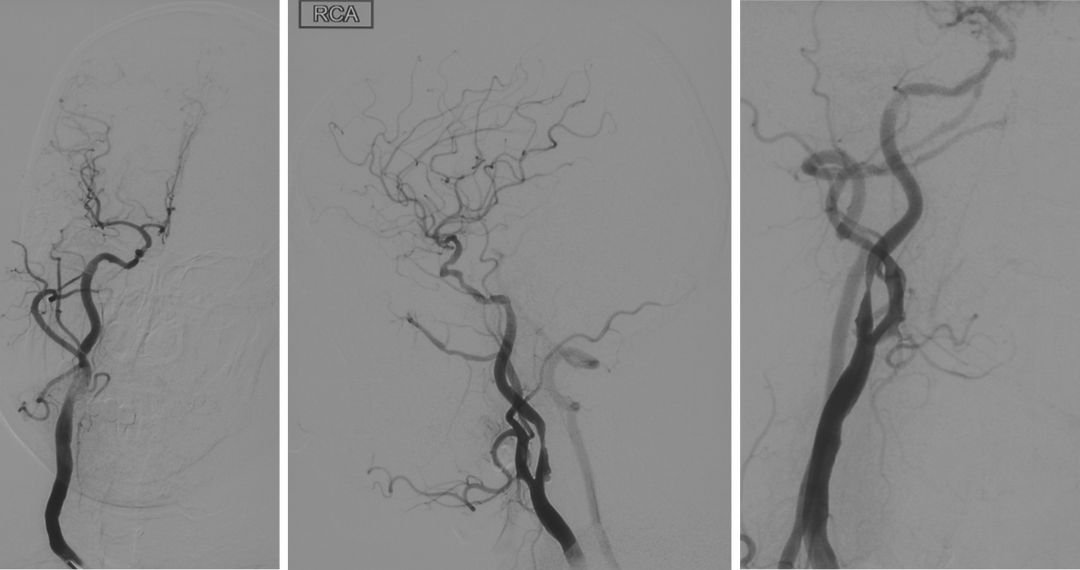

手术过程

在路图指引下将Filterwire保护装小心通过狭窄段,送入右侧颈内动脉岩段释放,顺保护装置微导丝将Wallstent 9.0*40mm支架于狭窄段,准确对位后于病变处释放。

顺保护装置微导丝将LitePAC5.0*30mm球囊小心通过狭窄段,准确对位后以10atm压力扩张球囊。

撤回保护装置及导引导管,封堵器封堵血管鞘,自然中和肝素,术后患者病情平稳,安全返回神经内科病房。